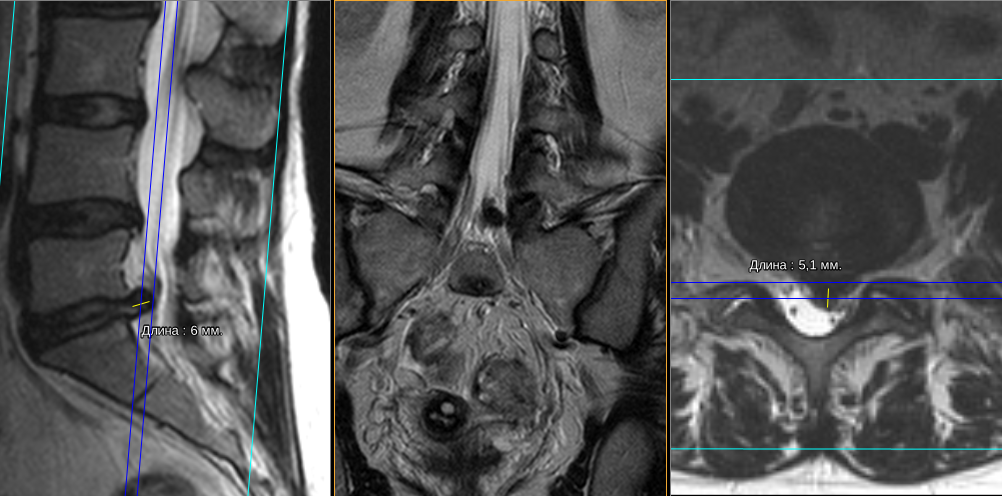

Грыжа Диска L5 S1 Фото

Грыжа Диска L5 S1 Фото 108 фотографий